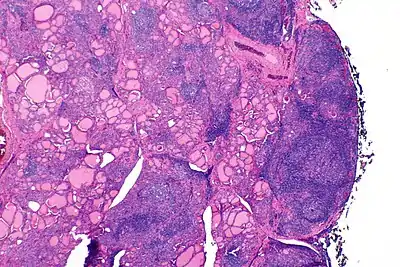

![]() | |

| The thyroid of someone with Hashimoto's thyroiditis as seen with a microscope at low magnification | |

Gross morphological changes within the thyroid are seen in the general enlargement, which is far more locally nodular and irregular than more diffuse patterns (such as that of hyperthyroidism). While the capsule is intact and the gland itself is still distinct from surrounding tissue, microscopic examination can provide a more revealing indication of the level of damage.[42]

Histologically, the hypersensitivity is seen as diffuse parenchymal infiltration by lymphocytes, particularly plasma B-cells, which can often be seen as secondary lymphoid follicles (germinal centers, not to be confused with the normally present colloid-filled follicles that constitute the thyroid). Atrophy of the colloid bodies is lined by Hürthle cells, cells with intensely eosinophilic, granular cytoplasm, a metaplasia from the normal cuboidal cells that constitute the lining of the thyroid follicles. Severe thyroid atrophy presents often with denser fibrotic bands of collagen that remains within the confines of the thyroid capsule.[42]